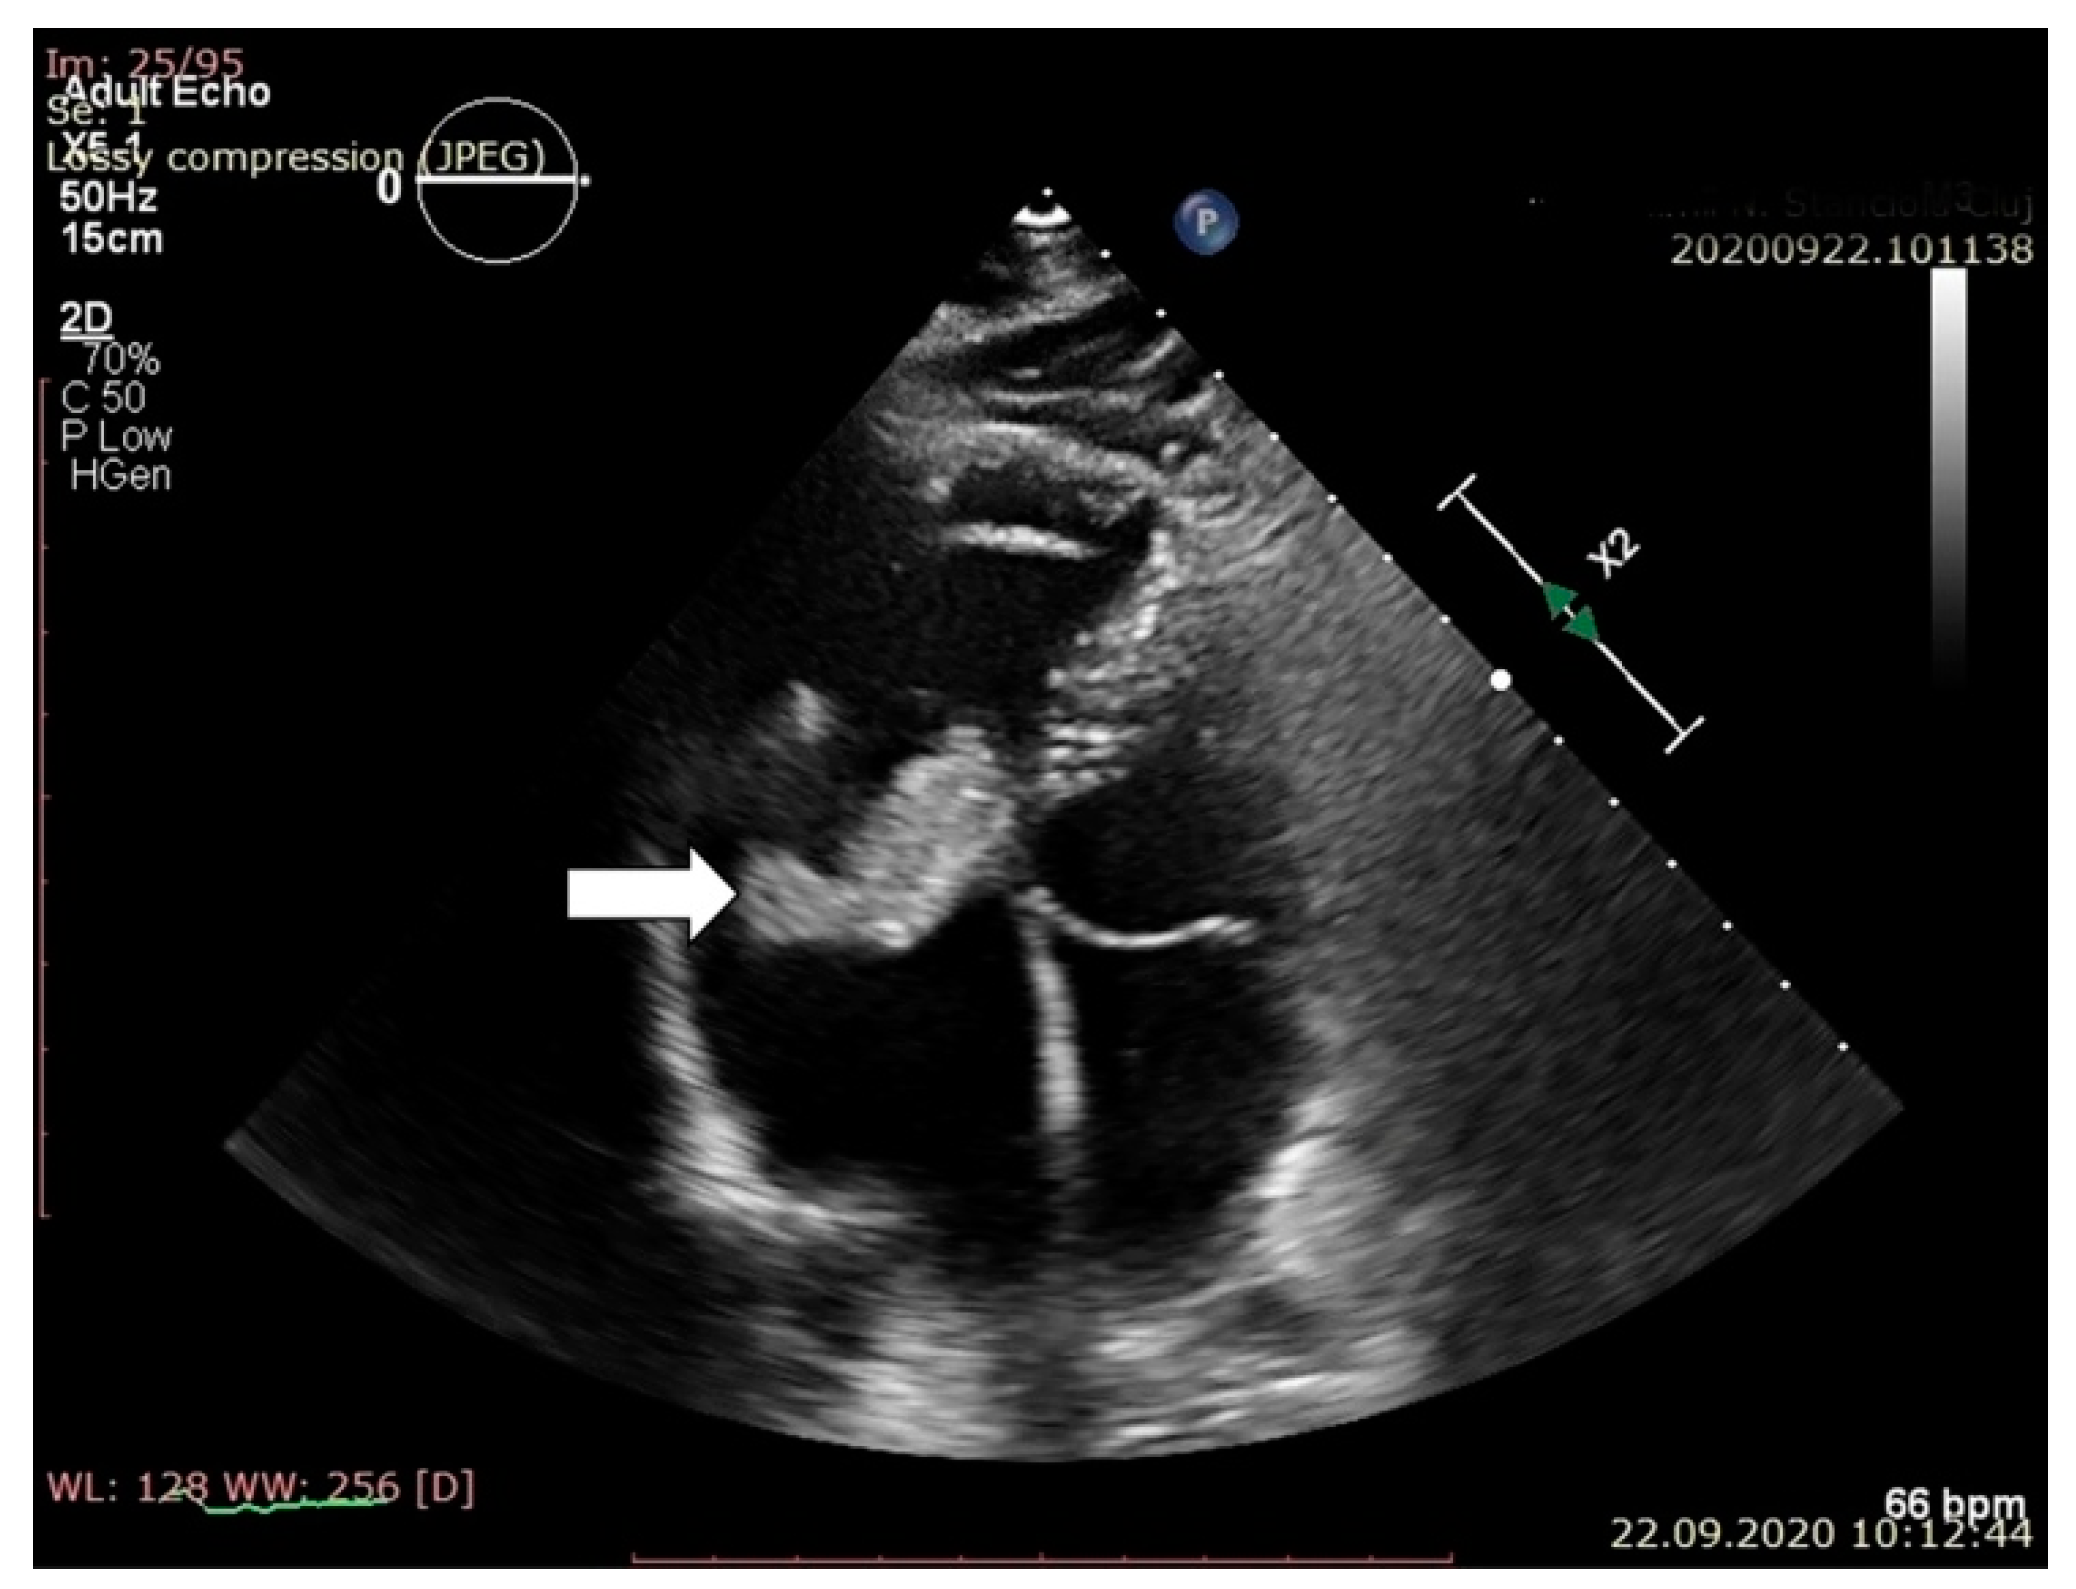

2. Case Report